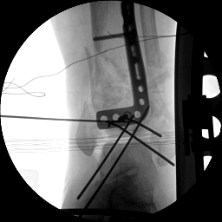

1.CO外固定半環(huán)連接跟骨穿針并通過CO接骨機器人配套的連接桿與CO接骨器人中間機械臂相連,調(diào)整機械臂,進(jìn)行骨折端初步復(fù)位,C臂確認(rèn)復(fù)位滿意,關(guān)節(jié)間隙拉開。

連接CO接骨機器人

牽拉復(fù)位

初步復(fù)位后X線